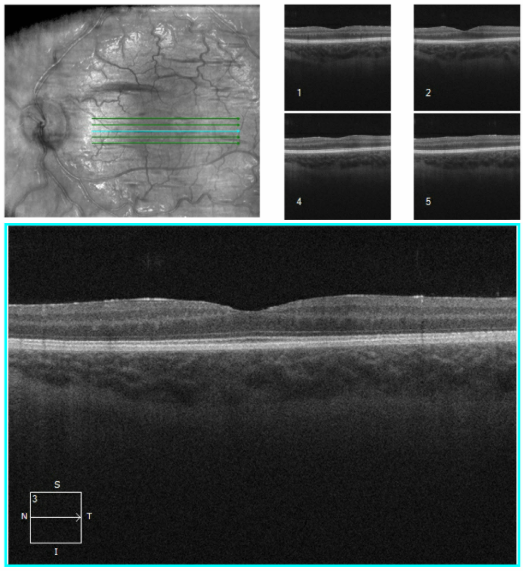

Please find below some images from the case:

OCT from early Jan 2026, when she first re-presented with vision loss in the left eye and disc edema. Very poor quality with poor fixation, but you can get a better sense of the left optic disc edema from the macular images.

Better quality OCT from the end of Jan after the shunt placement. The macular rasters don't catch the disc this time, so it's hard to compare, but I'd say the edema has clearly improved.

There was an OCT done both pre- and post- shunt revision. The pre-op OCT has so much movement artifact, it is difficult to interpret, but you can still see the disc edema subjectively. The post-op OCT shows significant atrophy with an RNFL of around 76 I think. The cross sectional images show a reduction in the edema as well.